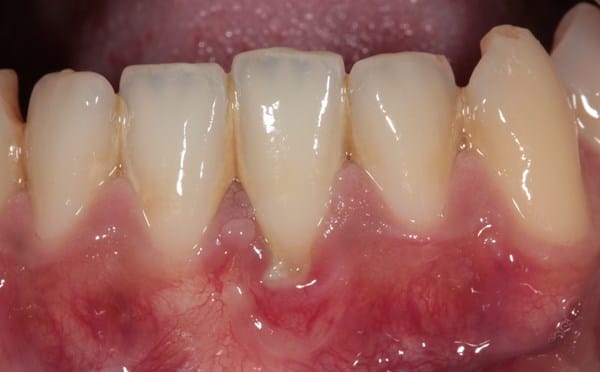

Hace unos meses me salían unas rayas en las encías y en la lengua que no me permitían comer adecuadamente, pero resulta que después de 5 días desaparecían hasta pensé que no me Ivan a salir más pero en estos días eh estado así mismo, no es por falta de alimentación porque creo que como muy bien hasta eh estado tomando Vitaminas C .